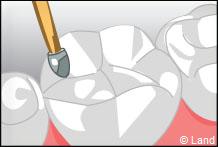

Il est réalisé en une séance. Il imite parfaitement la dent.

La base de remboursement varie selon l’importance de la carie.